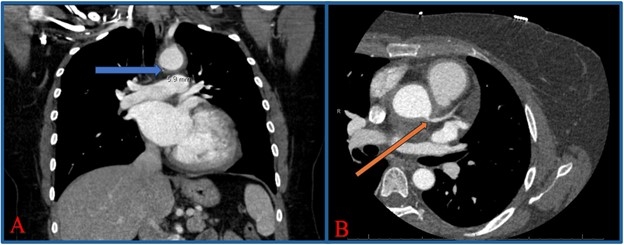

A healthy 42-year-old woman with a BRCA mutation presented for breast cancer screening via a magnetic resonance imaging (MRI). This revealed cardiomegaly, for which she was referred to our hospital for workup. Her exam revealed a widened pulse pressure (70 mmHg) and a diastolic murmur at the right upper sternal border. Subsequently, a computed tomography (CT) and transthoracic echocardiogram showed perivascular fat-stranding concerning for aortitis (Figure 1A) and aortic regurgitation (AR) with left ventricular (LV) dilation and dysfunction, respectively. These findings were confirmed with a cardiac MRI (Figure 2) and transesophageal echo. Subsequent coronary CT angiogram ruled out aortic dissection but revealed 70% ostial left main (LM) coronary artery stenosis (Figure 1B), which was confirmed on coronary angiogram (Figure 3A).